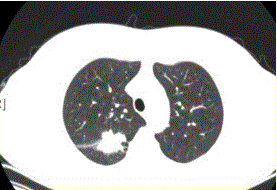

问题 患者女,54岁,无症状,常规体检透视时发现右上肺阴影。既往无结核病史。体格检查阴性。CT结果如下图。 本病例可见的征象包括

选项 A.分叶征 B.毛刺征 C.胸膜凹陷征 D.空泡征 E.含气支气管征 F.钙化

答案 ABCE

解析 ABCE